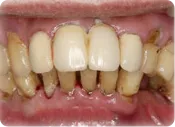

歯周炎

中等度歯周炎

骨(歯槽骨)が歯根の長さの1/3~1/2まで消失したもの。

炎症がさらに悪化すると歯槽骨が溶けて歯根部が露出し、冷たいものや熱いものがしみたりする事もあります。

歯石が歯周ポケットの奥にますます付着し、歯肉が腫れ膿が出て来ます。口臭も徐々にひどくなり、歯を支えている骨(歯槽骨)の吸収により歯がグラグラ動きはじめます。

重度歯周炎

骨(歯槽骨)が歯根の長さの1/2以上消失したもの。

歯槽骨がほとんど無くなり歯根が露出し、最後には抜けてしまいます。歯周病は重度に進行すると歯を抜かなければならなくなり、歯を失う最も大きな原因です。 虫歯のように鋭い痛みがなく徐々に進行しますので、知らないうちにかなり進行しているという方も大勢おられます。